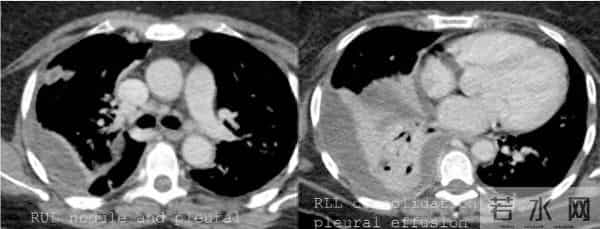

胸部CT血管造影显示:双侧肺实质内有不规则结节,右侧有中等量复杂性胸腔积液,还伴随肺不张,但没有肺栓塞的迹象。床边超声进一步确认,右侧胸腔里的积液已经形成了分隔的包裹性积液。

图1 CT显示右侧复杂性胸腔积液伴有肺部结节